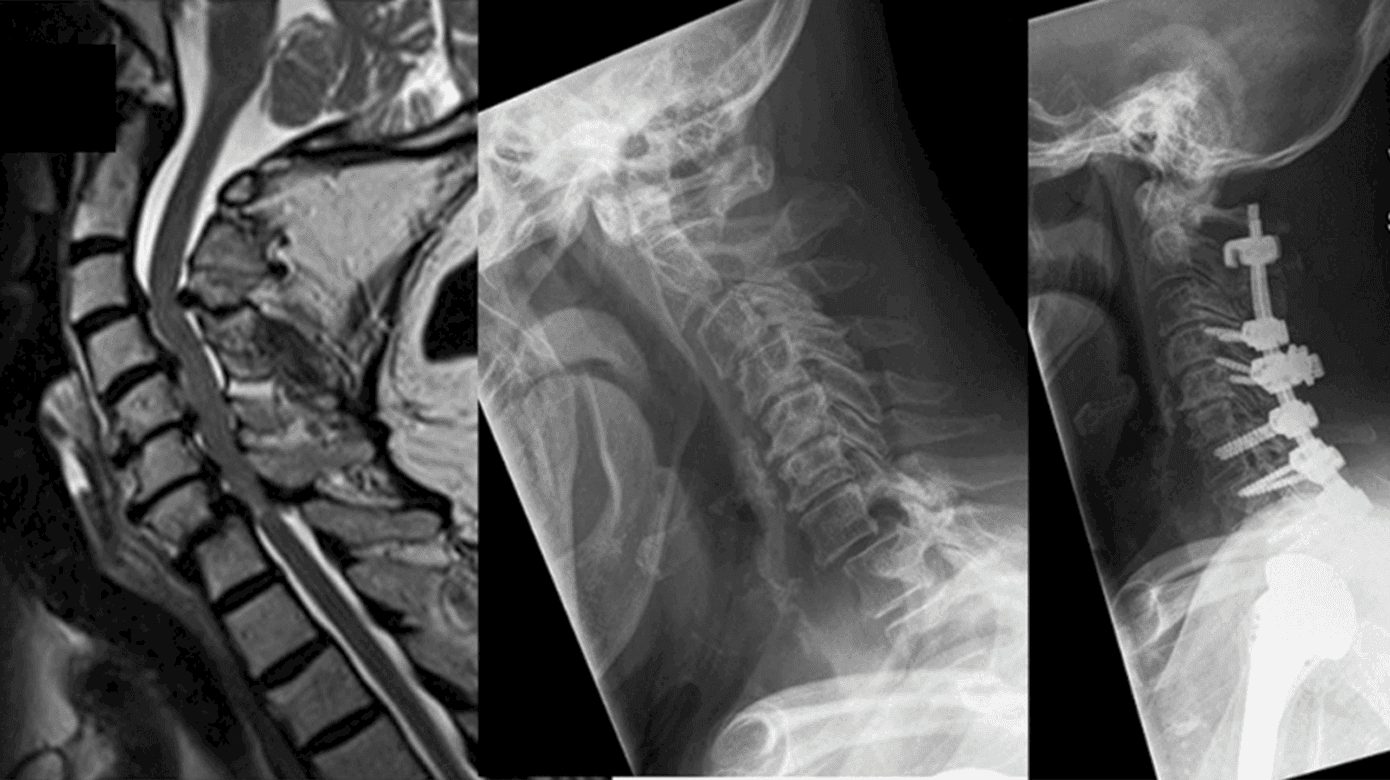

Cervikal spondylotisk myelopati (CSM) er en hyppigt forekommende progressiv tilstand, der er kendetegnet ved aldersrelaterede degenerative forandringer i columna cervicalis, hvilket resulterer i gradvist ophævet liquorflow og efterfølgende kompression af rygmarven og/eller de omgivende blodkar [1, 2]. Kompressionen opstår med baggrund i den spondylotiske ryg med degenerative forandringer omkring diskus, vertebra, facetled og ligamenter medførende nedsat plads i spinalkanalen (Figur 1) [2, 3].

MR-skanning af columna cervicalis er den foretrukne billedmodalitet og et uundværligt redskab i udredningen af CSM (Figur 3). Ved konventionel MR (T1/T2/STIR-vægtet) kan klinikeren verificere graden af degeneration (spondylose, ossifikation af posterior longitudinale ligament, diskusprolaps, hypertrofi af lig. flavum, osteofytdannelse), rygmarvskompression, ændringer i spinalkanalens diameter og ændringer i signalintensiteten (Figur 1) [2, 22, 23]. Bl.a. kan signalændringer i rygmarven have en prognostisk betydning for patienten. På T2-vægtet optagelse vil en lav signalintensitet uden skarp afgrænsning generelt repræsentere potentielt reversibel myelopati. Derimod vil høj signalintensitet på T2- og lav signalintensitet på T1-vægtede billeder ofte repræsentere irreversibel myelopati såsom kavitation, neuralt vævstab, myelomalaci, nekrose og spongiforme ændringer i den grå substans [14, 18, 22, 23]. Herudover er MR nødvendig for at udelukke differentialdiagnoser til CSM såsom tumor, syringomyeli, demyeliniserede plaques mv. (Figur 3). Det er vigtigt at understrege, at MR-skanningens fund ikke kan stå alene, da det ikke er ualmindeligt, at asymptomatiske patienter har billeddiagnostiske tegn på CSM [9, 23, 24].

Den kirurgiske behandling bygger på en pladsgivende operation med dekompression af nerverne samt evt. korrektion af sagittal alignment [25]. Der findes tre operative muligheder: en anterior, posterior og kombineret adgang. Litteraturen har trods adskillelige forsøg ikke kunnet påvise en entydig/overbevisende overlegenhed ved den ene tilgang sammenlignet med den anden. Valget beror i stedet primært på tilstedeværelsen af cervikal kyfose/lordose, anatomisk placering af stenosen, antal afficerede segmenter samt operatørens præference [15, 26, 27]. De operative indgreb kan med eller uden instrumenteret fusion indbefatte korpektomi, laminektomi, diskektomi, laminoplastik samt fusion ved tab af sagittal alignment [26].